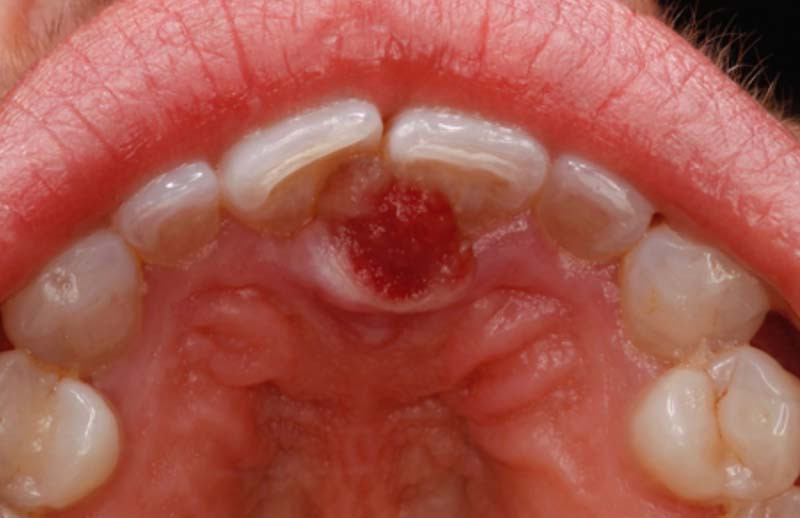

Motif de la consultation. Patiente de 55 ans venue consulter pour une tumeur gingivale palatine.

Histoire de la maladie. La patiente a constaté l’apparition 3 mois auparavant d’une tumeur juste en arrière de 11 et 21. La tumeur, qui était initialement asymptomatique, a augmenté très lentement de volume, puis elle a présenté des épisodes de saignement et de douleurs pulsatiles.

Examen clinique. On observait une tumeur gingivale sessile, hémisphérique, de 8 mm de diamètre, siégeant sur la gencive palatine, au contact de 11 et 21. Elle donnait l’impression de refouler la muqueuse saine et sa surface rouge était occupée par une ulcération.